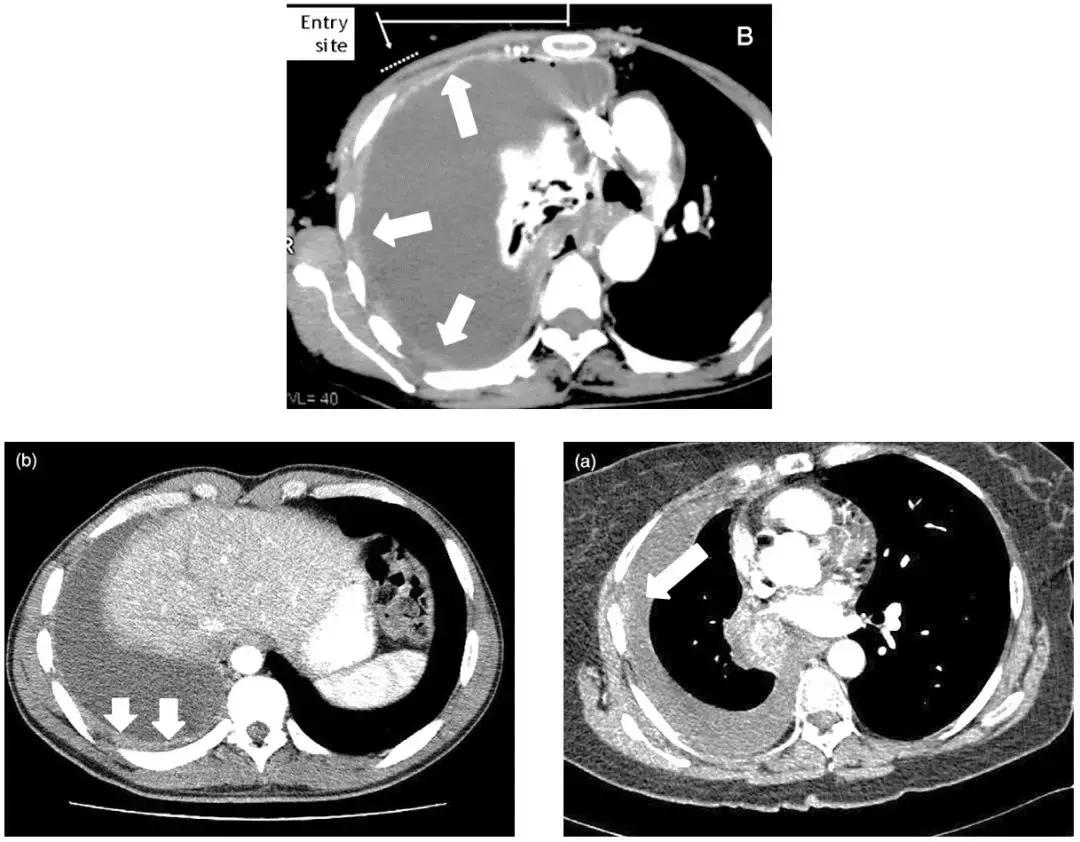

仔细阅读CT,识别胸膜增厚点是成功的第一步

我们可以看到CT图像上,选择胸膜较厚的地方来进行穿刺,阳性率较高,反之阳性率较低(箭头为增厚部位)。

适合盲穿活检的胸腔积液 >>

胸膜弥漫性增厚,在相对比较弥漫的地方确定安全的进针点进行穿刺。

如下图,选择增厚、病变比较明显的地方进行穿刺,阳性率较高。